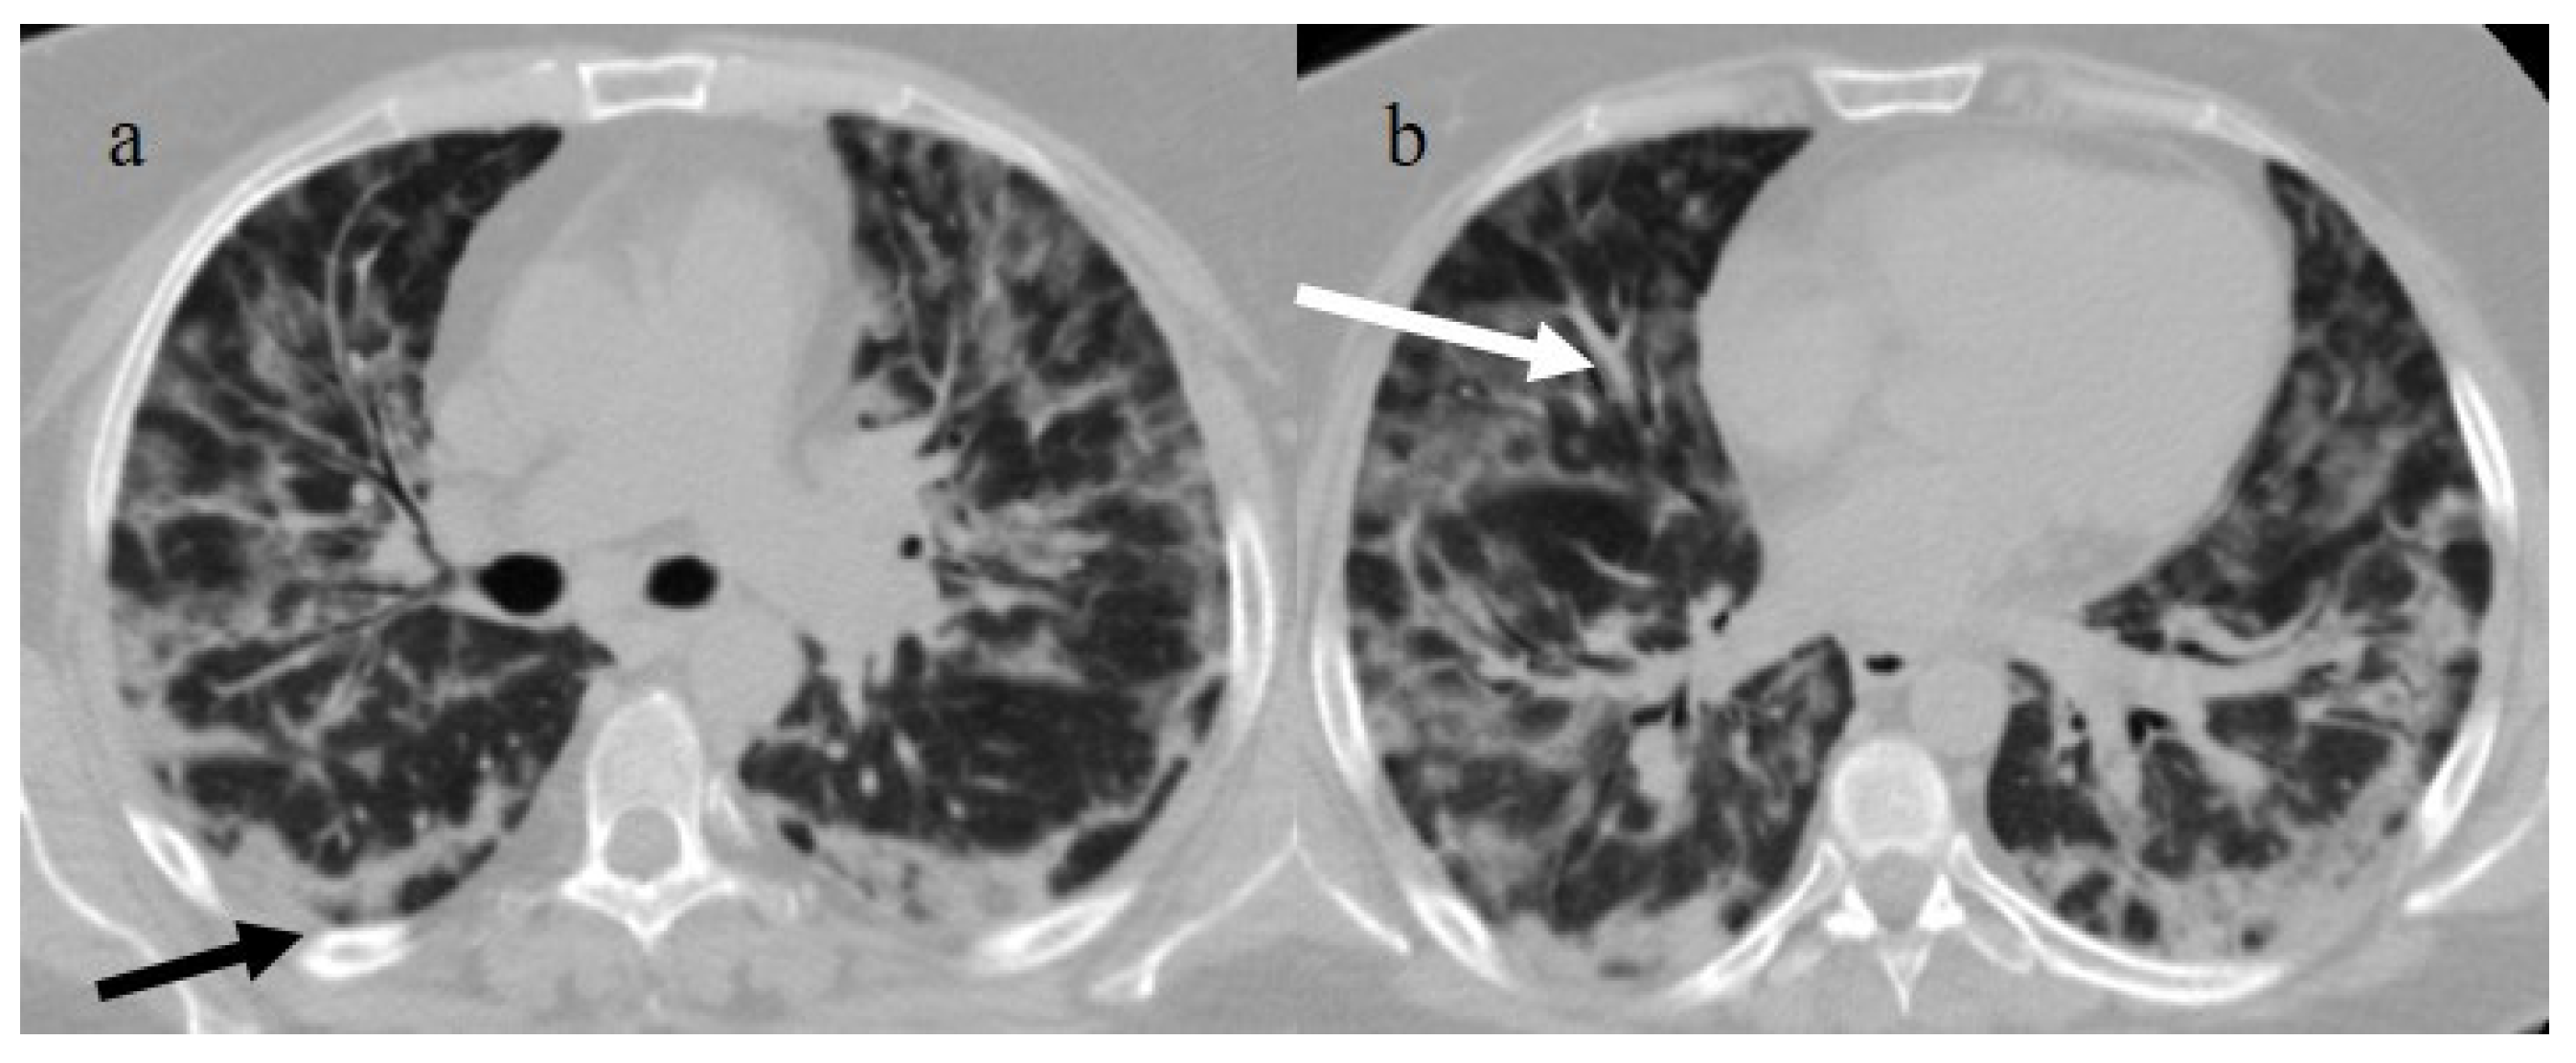

| Typical Appearance | GGOs with a crazy-paving pattern and consolidations in a peripheral and posterior or central-peripheral distribution; multilobar involvement; vascular enlargement, the halo and reversed halo sign; subpleural and parenchymal bands; and architectural distortion. They were predominant since the Delta wave. |

| Indeterminate Appearance | GGOs and consolidations with a unilateral, central, or upper-lobe distribution. |

| Atypical Appearance | Lobar consolidation, lung nodules or masses, miliary patterns, tree-in-bud patterns, cavitation, pleural effusion, central distribution, and lymphadenopathy. Atypical appearances were predominant during the Omicron waves. |

| Typical appearance | From the wild-type to the Delta variant. | Askani et al., 2022 [67] | The Delta variant presented more frequent typical features with more extensive lung involvement than the Omicron variant. The Omicron variant was more frequently associated with the absence of pneumonia. |

| Inui et al., 2021 [68] | Typical findings were characteristic of the wild type to the Delta variant. GGOs with consolidation and repair changes were more frequent in the Delta variant. The Delta variant also showed more rapid pneumonia progression than the wild-type and Alpha variants. | ||

| Ito et al., 2022 [54] | Peripheral GGO distributions were more frequent in the Alpha and Delta variants than the Omicron variant. | ||

| Kirka et al., 2022 [27] | Typical features were found in 40.8% of patients with the wild-type variant and 1.7% of patients with the Omicron variant. | ||

| Lee et al., 2023 [28] | Typical CT patterns were more frequent in the Delta group (76%) than in those with the Omicron variant (42%). | ||

| Yang et al., 2022 [78] | Of patients with the Alpha variant, 86.84% presented typical COVID-19 pneumonia CT features. | ||

| Yoon et al., 2023 [69] | Only 32% of patients with the Omicron variant presented typical findings, compared with 57% of the Delta variant cases. | ||